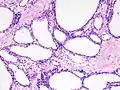

Pathologists classify serous cystic neoplasms into two broad groups. Those that are benign, that have not spread to other organs, are designated "serous cystadenoma".[5] Serous cystadenomas can be further sub-typed into microcystic, oligocystic (or macrocystic), solid, mixed serous-endocrine neoplasm, and VHL-associated serous cystic neoplasm. This latter classification scheme is useful because it highlights the range of appearances and the clinical associations of these neoplasms. Serous cystic neoplasms that have spread ("metastasized") to another organ are considered malignant and are designated "serous cystadenocarcinoma".

Pathology